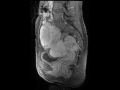

Krukenberg Tumors

MR images demonstrate large mass is arising in the pelvis apparently arising from both ovaries in a patient with known underlying GI malignancy, compatible with Krukenberg tumors.